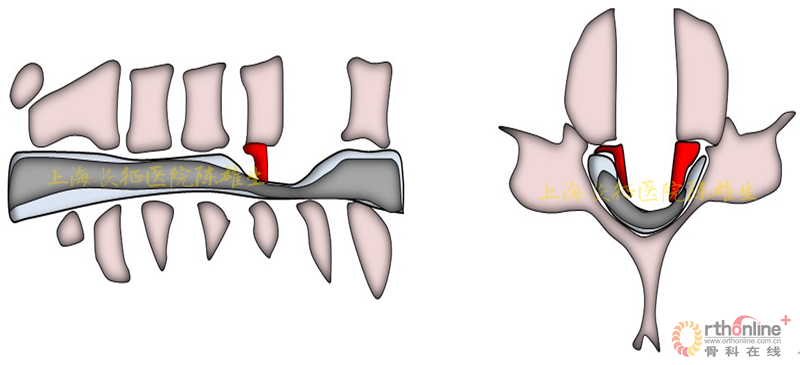

3.2.2骨化物漂浮,初步缓解脊髓压迫

磨钻磨透骨化物周围骨结构;剥离子游离骨化物边界,使之漂浮,初步缓解脊髓压迫(图13)。

图13